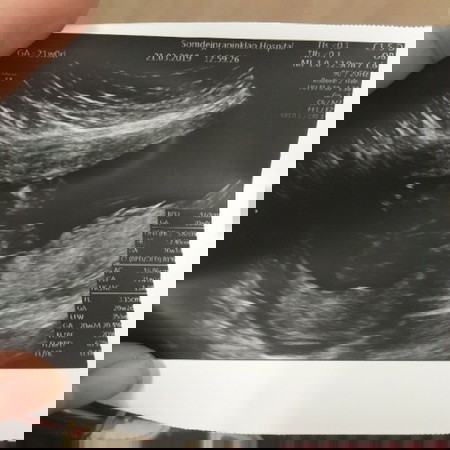

เมื่อวันที่21ที่ผ่านมา หมอซาวน์เพศน้องหมอบอกน้องแข็งแรงดี แต่พอซาวน์ไปถึงอวัยวะเพศหมอบอกว่ายังเห็นไม่ชัดไม่100%ทั้งๆที่น้องก็อ่าขาไม่ได้หนีบอะไร หมอบอกว่าเหมือนจะผู้หญิง แต่ไม่100% ตอนที่ซาวน์ 21วีค ค่ะ เห็นบางคนบอก13วีคขึ้นไปก็เห็นชัดเจนแล้ว ขอคำแนะนำหน่อยค่ะ อยากทราบเพศลูกจริงๆ